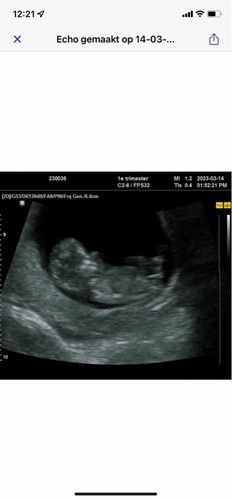

Op deze echo was ik 11+4 weken ☺️ ben benieuwd wat jullie denken te zien!